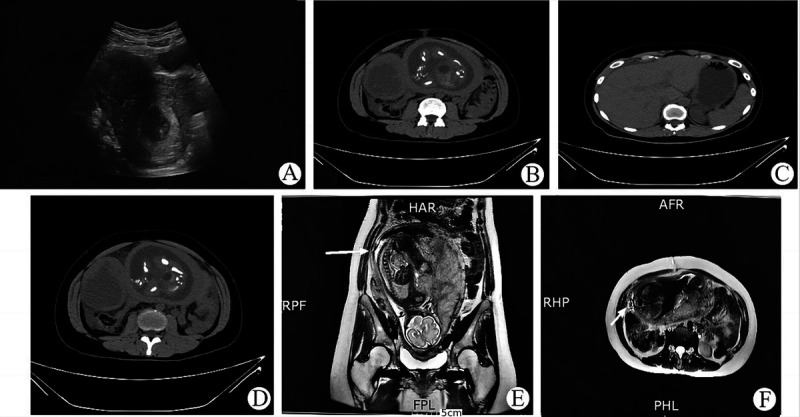

In this article, we report a case of spontaneous ruptured pyomyoma during pregnancy with successful delivery after myomectomy. A 35-year-old pregnant female (27 weeks of gestation) presented with lower abdominal pain. The patient had a history of uterine fibroids. Ultrasound, computed tomography, and magnetic resonance imaging confirmed a spontaneous ruptured pyomyoma (maximum diameter: 12.6 cm). Myomectomy was performed, and her abdominal distension and pain were significantly improved within 1 day; the condition of the fetus was normal. One month after surgery, severe tenderness was detected in the lower right side of the uterus. Considering the higher risk of uterine rupture and associated complications, a cesarean section was performed. The mother and neonate were discharged 3 and 42 days after delivery, respectively, in good condition. Myomectomy for spontaneous ruptured pyomyoma during pregnancy may be feasible and extend gestational age to improve outcomes for the mother and neonate.